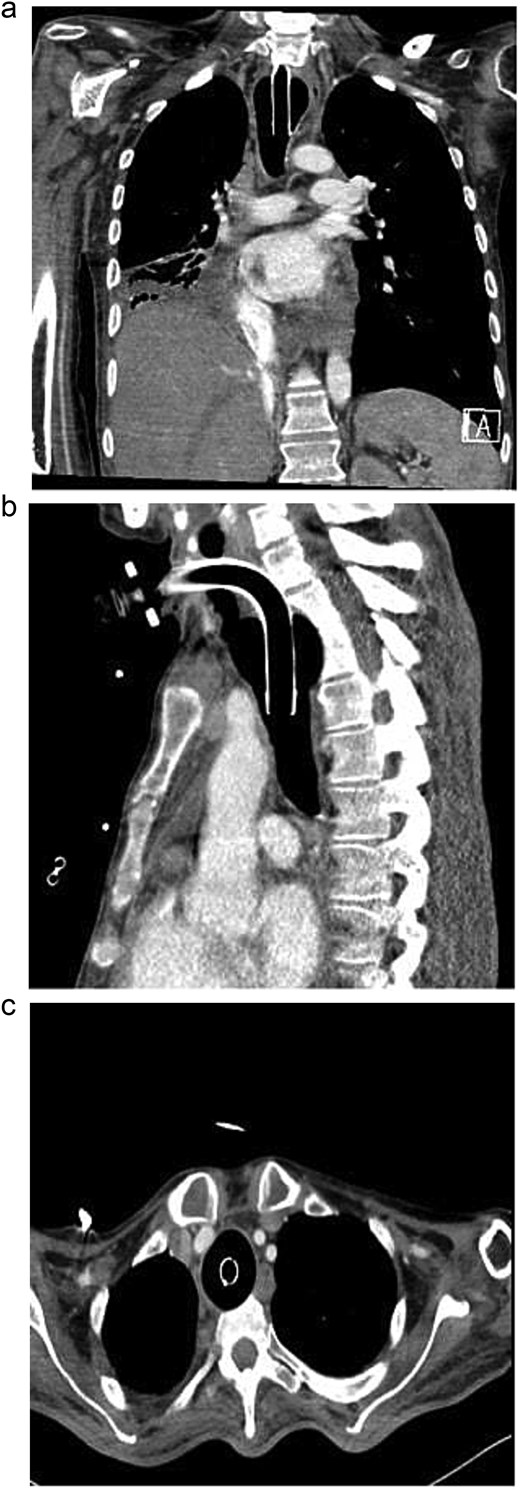

A 40-year-old male who is known to have amyotrophic lateral sclerosis was admitted to the intensive care unit for ventilatory support. He underwent surgical tracheostomy for long-term mechanical ventilation dependence, a double-lumen tracheostomy tube with an internal diameter of 8 mm and a maximum cuff pressure of 25.4 mm was inserted, post-operative chest X-ray confirmed tube placement (Fig. 1). Six months later, the otolaryngologist on-call was consulted regarding ventilation leak that was evident in the ventilator. Flexible endoscopy through the stoma revealed a significantly dilated trachea with a posterior groove. The tube was changed to size 7 with an extended distal length of 49 mm to bypass the dilated segment. A temporary improvement was noted; however, the leak was noted again, with an inspiratory tidal volume of 800, and an expiratory volume of 135, the cuff pressure was gradually elevated to overcome the leak reaching a maximum of 40 mmHg, with the cuff seen over-inflated in routine supine chest X-ray (Fig. 2). Multiple tube obstruction events happened later, which required rigid bronchoscopy examination under general anesthesia to assess and relieve the obstruction. Intraoperative examination revealed that the obstruction was caused by a large dry blood clot, withdrawal of the tube to examine the trachea further revealed a large posterior tracheal wall defect with exposed thoracic vertebrae. The patient underwent a subsequent contrast-enhanced computed tomography scan (CECT) of the neck and chest which confirmed the intraoperative findings (Fig. 3). The leak was not improving by increasing cuff pressure, consequently, the decision was made to use an armored endotracheal tube size 8 at a lip level of 13 to bypass the defect. This has slightly improved the oxygenation and ventilation of the patient, but it did not eliminate the leak. The general poor health of the patient along with his do-not-resuscitate (DNR) status has led to deterring the decision of surgical tracheal wall repair. The patient was further diagnosed with sepsis due to multiple infection sources including his long-term suprapubic urinary catheter, he eventually had a cardiopulmonary collapse a few weeks later and passed away.

Axial contrast-enhanced chest CT with reformatted coronal and sagittal images showing fusiform dilation of the trachea with scalloping of the anterior surface of thoracic vertebral bodies. Moreover, no appreciable separating soft tissue layer between the tracheostomy cuff and the anterior surface of vertebral bodies.